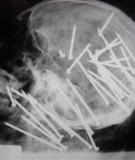

Đau mắt hột là bệnh lý chỉ tình trạng viêm giác mạc, kết mạc mắt mãn tính do vi khuẩn Clamydia Trachomatis gây ra. Nếu không được chữa trị có thể dẫn đến mù mắt. Đây là một bệnh khá phổ biến, có thể lây lan thành dịch, thường gặp nhất là ở những vùng thiếu nước sạch và có hệ thống vệ sinh phòng bệnh kém.

Đại cương Là trạng thái mọc khác thường của lơng mi, lơng mi thay vì hướng ra phía ngồi mà lại hướng về bên trong, đâm vào kết mạc, giác mạc gây viêm, loét, rất khĩ chịu cho mắt, thậm chí cịn cĩ thể bị mù. Sách ‘Bí Truyền Nhãn Khoa Long Mộc Luận’ (năm 1575) là sách đầu tiên dùng từ ‘Đảo Tiệp Quyền Mao’ để chỉ trạng thái lơng quặm. Đông y gọi là Tiệp Mao Đảo Nhập, Đảo Tiệp, Đảo Tiệp Quyền Mao, Đảo Tiệp Quyền Luyến. Nguyên nhân Đa số do mắt hột khơng điều trị...

MỤC TIÊU: 1.Kiến thức: - Mô tả các tật về mắt: cận thị, viễn thị: + Biểu hiện, nguyên nhân, cách khắc phục, cách phòng tránh. - Nhận biết các bệnh về mắt: đau mắt hột, đau mắt đỏ...: + Biểu hiện, nguyên nhân, cách phòng tránh.

I/ MỤC TIÊU: 1 / Kiến thức: Hiểu rõ nguyên nhân của tật cận thị , viễn thị và cách thức khắc phục Trình bày được nguyên nhân gây bệnh đau mắt hột , cách lây truyền và biện pháp phòng chống . 2 / Kỹ năng: Phát triển kỹ năng quan sát , nhận xét và liên hệ thực tế 3 / Thái độ : Giáo dục ý thức bảo vệ mắt , phòng tránh các bệnh về mắt . II/ CHUẨN BỊ: 1/ Giáo viên: Tranh phóng to hình 50.1 ; 50.2 ; 50.3 ; 50.4; Bảng phụ...

I. MỤC TIÊU. 1. Về kiến thức Khi học xong bài này, HS: - Nắm được các nguyên nhân của tật cận thị và viễn thị, cách khắc phục. - Nêu được nguyên nhân của bệnh đau mắt hột, con đường lây truyền và cách phòng tránh. - Biết cách giữ gìn vệ sinh mắt.

Viêm kết mạc là nhóm bệnh phổ biến nhất trong số các bệnh về mắt, chúng chiếm tới 70% trường hợp tới khám ở các phòng khám mắt. - Nhiều loại viêm kết mạc hay lây lan và thậm chí phát triển thành dịch, ảnh hưởng rất lớn tới quân số lao động và chiến đấu. - Bệnh mắt hột cũng là một trong những viêm kết mạc song do tính chất tổn thương đặc hiệu và sự đặc biệt về dịch tễ học cho nên được đề cập trong một bài riêng. ...